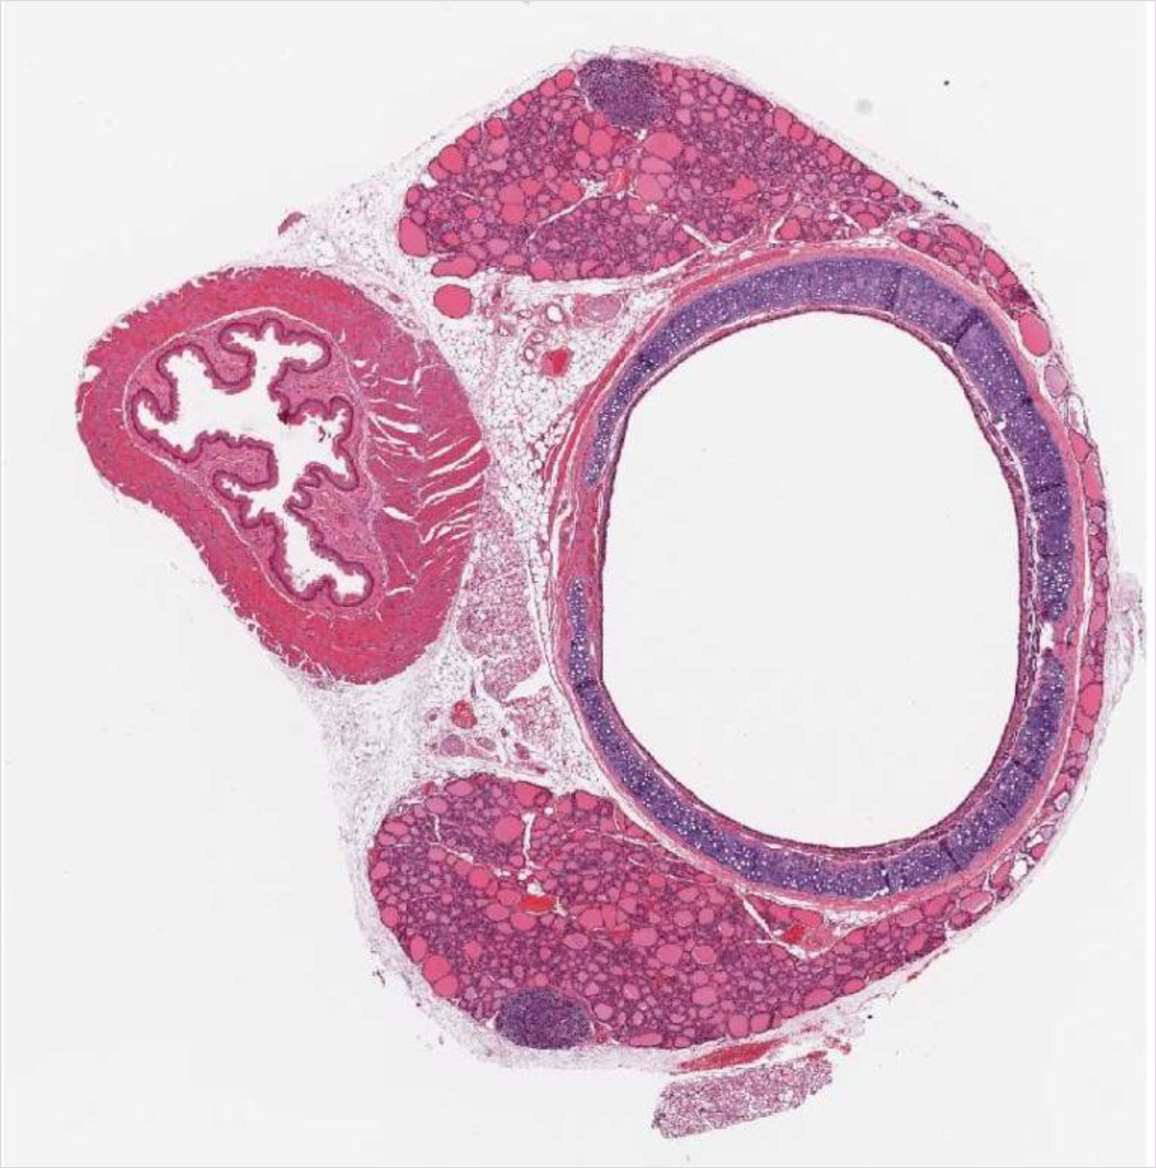

Organ Identification

Lymph node

1

2

3

4

5

61. Cortex,

2. Medulla,

3. Germinal center,

4. Cortex,

5. Lymphocyte,

9. CapsulaStomach